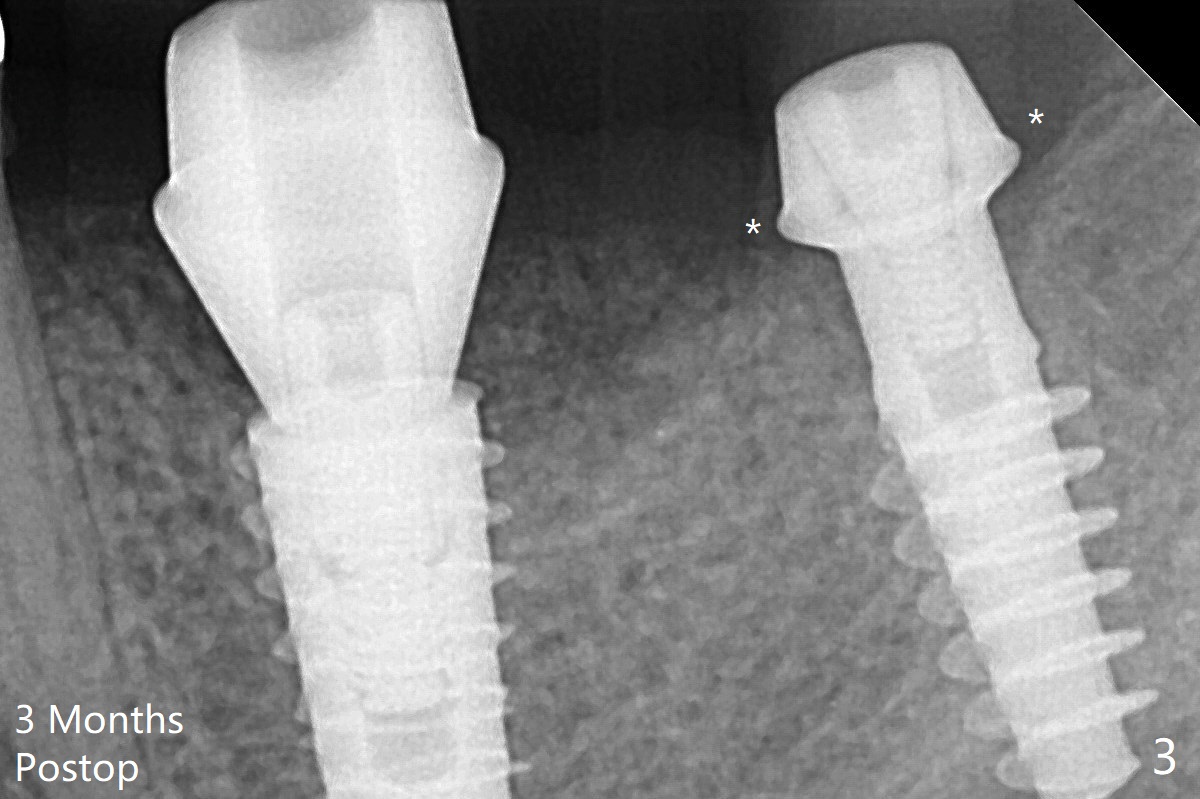

Because of supraeruption of the opposing teeth, the abutment at #19 is heavily reduced, whereas the Magicore is placed super low (Fig.2).  The latter may be backed up or crown lengthening is necessary.  In fact neither is necessary, since there is crestal bone loss at #18 nearly 3 months postop (Fig.3).  There is no difficulty in placing 4.5 mm healing cuff.